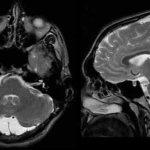

Несмотря на то, что полное восстановление нарушенных нервных клеток в головном мозге невозможно, все же детский орган в какой-то степени способен самовосстанавливаться. Регенерация поврежденной ткани не происходит, но образуются новые связи с осуществлением новых функций старыми нейронами.

Подобные связи образуются лишь в той структуре головного мозга, которая отвечает за память. Остальные функции, возложенные на мозг, необходимо стимулировать, что можно осуществить именно с помощью лечебного массажа и физкультуры.

За счет повышения активности мозговых аналитических центров головного мозга происходит образование новых связей, что влечет за собой восстановление двигательных функций.